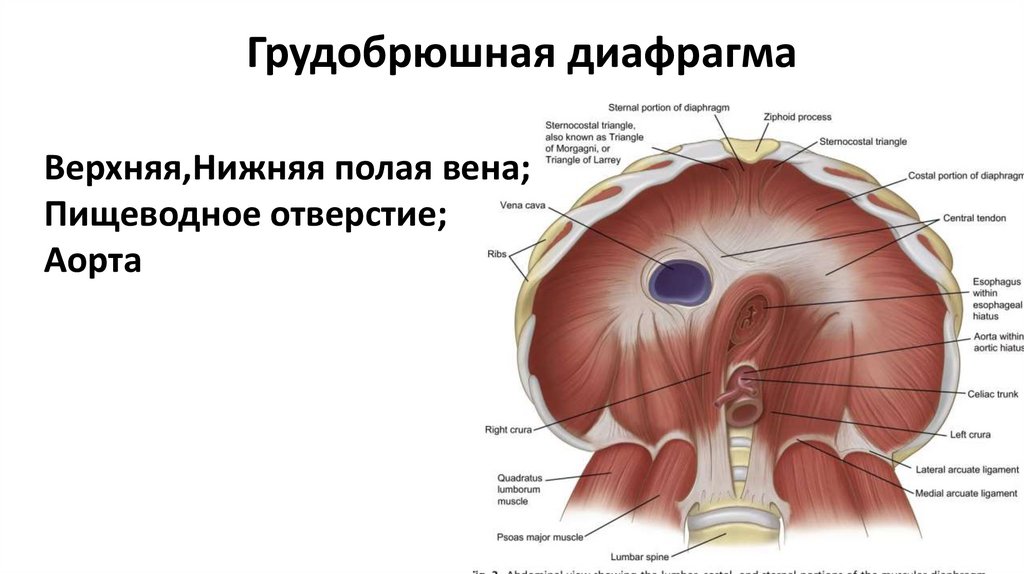

Анатомия диафрагмы и треугольника Бохдалека

Раздел: Визуальный дайджест